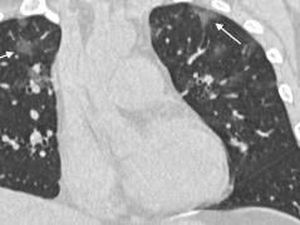

Sebuah laporan mengungkap penampakan paru-paru 2 pasien virus corona COVID-19 pertama di Italia. Keduanya adalah warga Wuhan yang sedang berlibur ke Eropa.